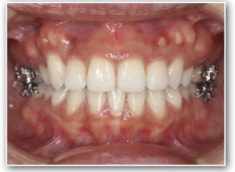

治療開始1年後